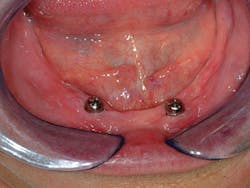

Another big reason most edentulous patients have not had implants is the constant promotion by newspapers, magazines, and TV of complex, extensive, and expensive techniques provided by some dentists and implant manufacturers. Yes, I agree that these complex plans are acceptable for some patients, but I'm convinced they're well beyond the budgets of most Americans. Thousands of edentulous patients have not been introduced to less expensive and less invasive implant treatment procedures. The majority of dentists are not using implants for edentulous patients. This treatment need is enormous, and it's only waiting for dentists to educate patients and make dentures more successful (Figures 1-3).

Figure 1 - Initial healing on two conventional diameter root form implants planned to help support and retain a mandibular complete denture.